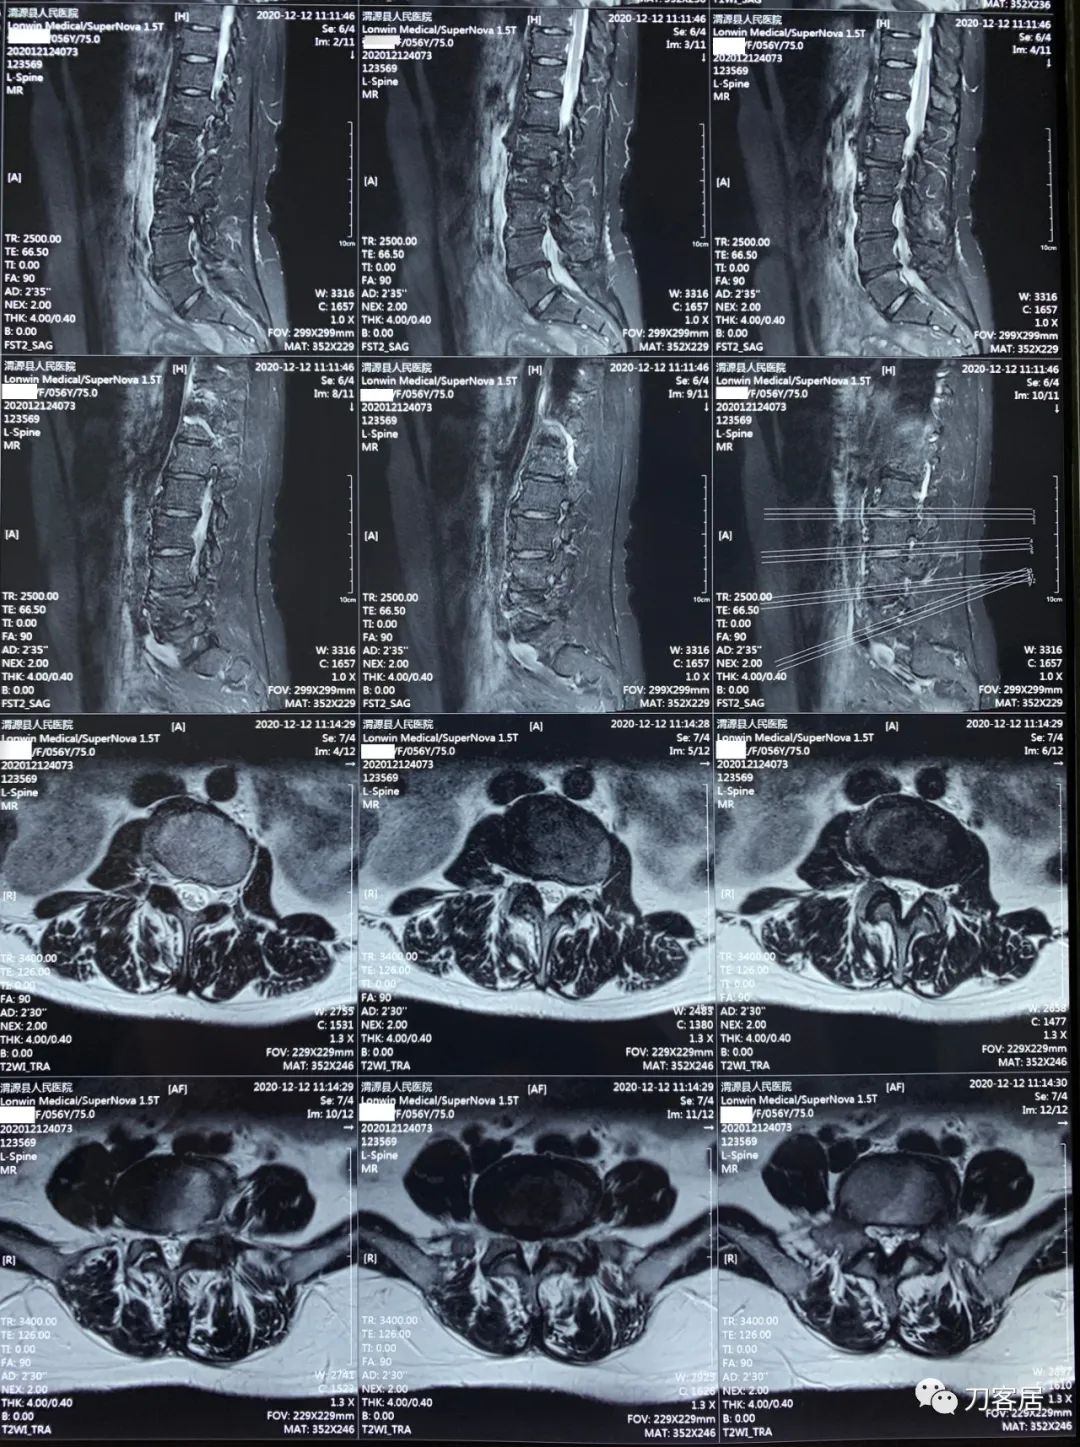

2021年12月12日去渭源县医院做颈椎腰椎MRI,提示1.腰椎侧弯畸形并骨质增生,2. L5S1椎体终板炎(I型), 3. L1-S1椎间盘变性并腰2-4,腰5骶1椎间盘膨出,腰4-5椎间盘突出并相应平面继发性椎管狭窄。2020年12月中旬于渭源县医院行骶管注射2次6针后睡眠改善,

2021年5月17日,西京医院骨科门诊找我就诊,自带影像学检查资料提示腰椎侧弯,腰3-4,腰4-5椎间盘突出,黄韧带肥厚,椎管狭窄。

建议其查双光子骨密度,骨盆正位片以及腰椎间盘平扫。腰椎正侧位X线片以及动力位片,站立位脊柱全长正侧位X线片,以了解其是否有骨质疏松,并了解脊柱侧弯情况,腰椎局部X线表现情况和腰椎间盘突出和椎管狭窄情况。

从这个患者的影像资料分析,颈椎间盘突出问题不大,没有明确的上位神经元损伤表现,所以,不考虑颈椎和胸椎问题。腰椎侧弯畸形,但不严重。因为存在腰椎侧弯,使得腰椎MRI在扫描切面的时候,显示的椎间盘突出或椎管狭窄会有一定的误差,所以,又加做了经椎间盘的CT平扫,影像表现并不严重,综上,腰椎间盘突出,腰椎管狭窄,腰椎侧弯,不考虑手术治疗。同时,患者的主要痛苦是心理疾病,而不是器质性疾病,所以,以心身疾病治疗为主。虽然患者骨密度检查结果提示正常,但X线片显示骨质疏松,且其症状也与骨质疏松的症状有符合之处,比如静息痛,不能入睡,动作及姿势变换时痛加重等,所以,给予实验性抗骨质疏松治疗,以观疗效。